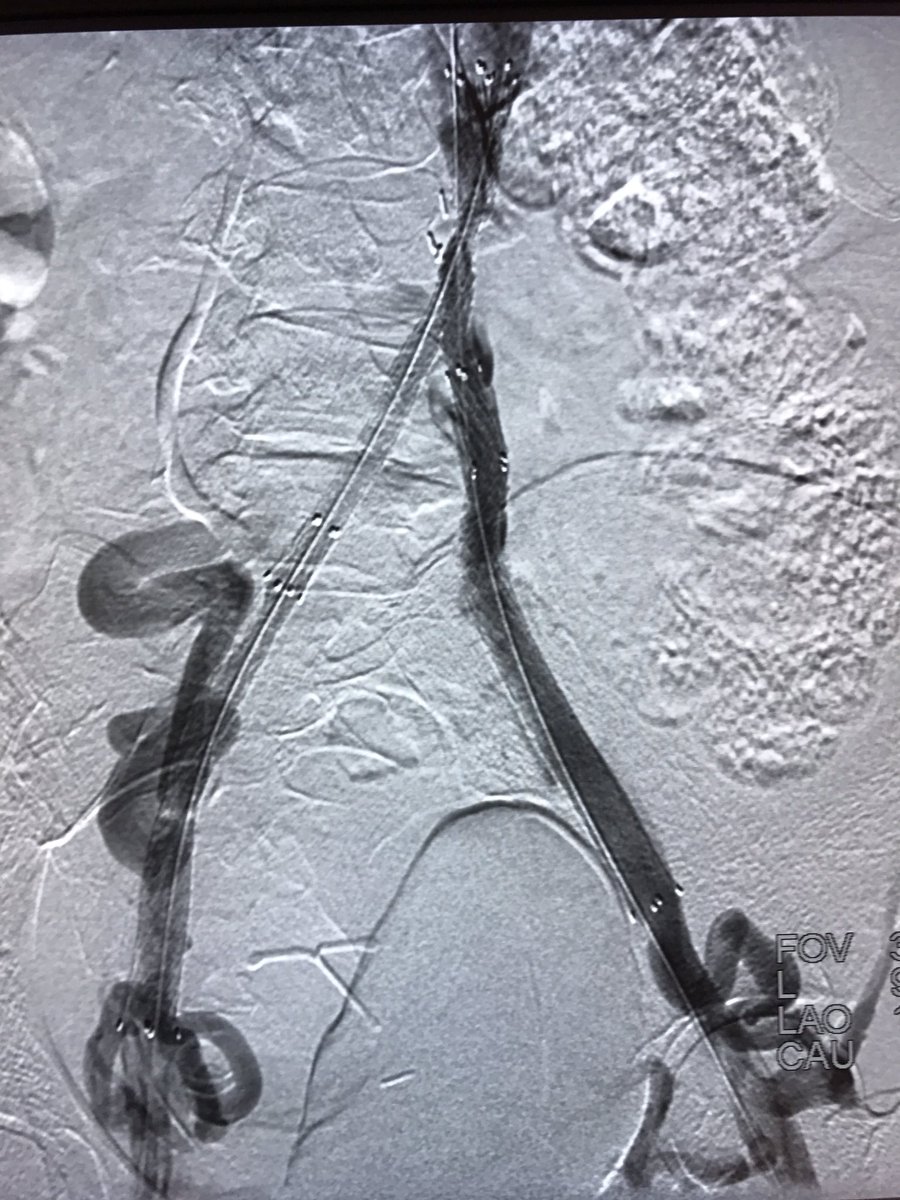

@IvcFilterClinic

Went old school snare and sheath with this #filterOUT | #iRad #bonanzatheme #IRmusicvideos